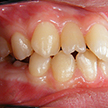

4. 術前右側

下顎前突とまでは言えませんが、上顎が明らかに下顎と比較して劣成長です。年齢的にも上顎の成長はほぼ終了し、下顎の成長は継続しますので、より顕著となり、本当に下顎前突になると考えられます。